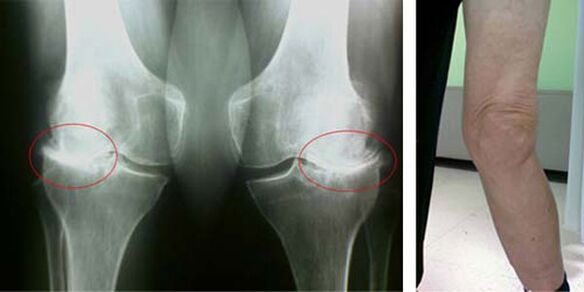

The initial stages of the occurrence of such pathology as osteoarthritis of the knee joint do not appear visually in any way. However, after some time the patient notices signs of knee deformity, as well as a characteristic curvature along the axis of the lower leg (directed inwards). There is also a crunch when you have to bend your legs.

The presence of pain, limited movement in the knee makes a person see a doctor and undergo an examination. To do this, he must pass tests and take an X-ray of the diseased joint. If these measures are not sufficient to confirm osteoarthritis of the knee, then magnetic resonance imaging is performed. Based on the collected data, the doctor chooses the best methods of treatment.